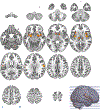

Results: Responses to sweet stimuli were associated with increased activity in regions associated with taste, sensory integration, and reward processing. These taste-evoked responses were modulated by context. Longer fasts were associated with higher posterior cerebellar, thalamic, and striatal activity. Greater self-reported hunger was associated with higher medial orbitofrontal cortex (OFC), dorsal striatum, and amygdala activity and lower posterior cerebellar activity. Higher BMI was associated with higher posterior cerebellar and insular activity.

Conclusions: Variations in fasting time, self-reported hunger, and BMI are contexts associated with differential sweet stimulus responses in regions associated with reward processing and homeostatic regulation. These results are broadly consistent with a hierarchical model of taste processing. Hunger, but not fasting or BMI, was associated with sweet stimulus-related OFC activity. Our findings extend existing models of taste processing to include posterior cerebellar regions that are associated with moderating effects of both state (fast length and self-reported hunger) and trait (BMI) variables.